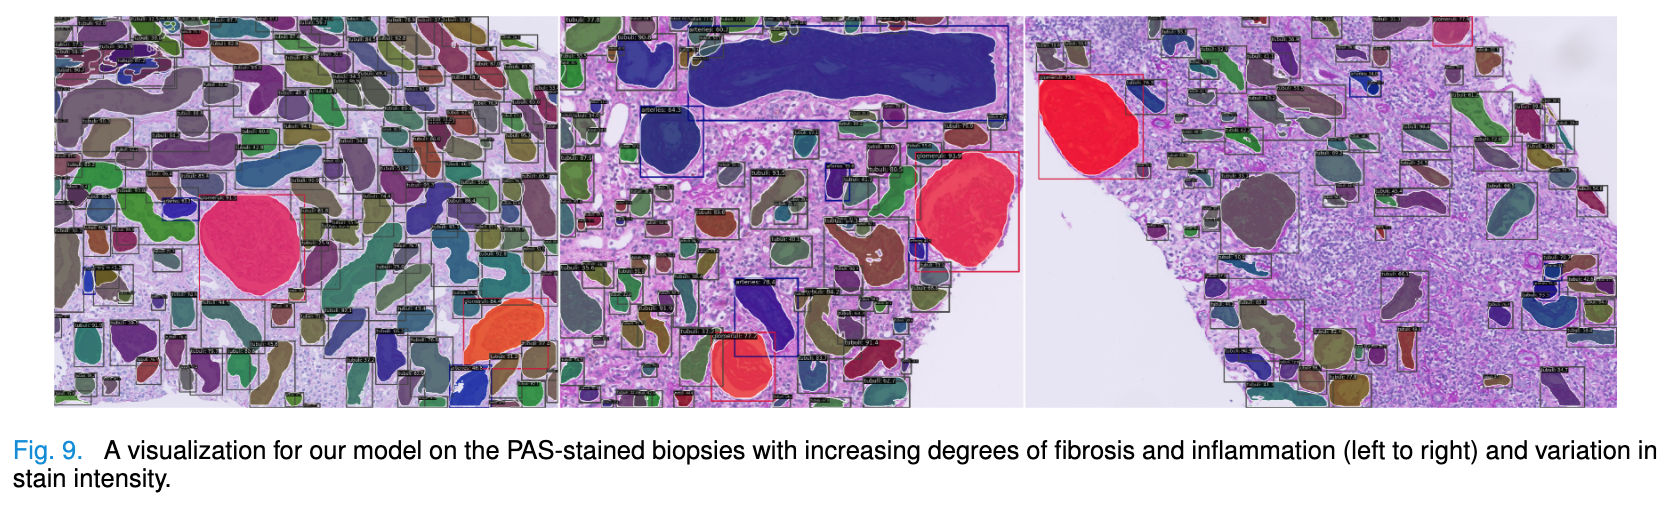

| Advances in Kidney Biopsy Structural Assessment through Dense Instance Segmentation Authors Zhan Xiong, Junling He, Pieter Valkema, Tri Q. Nguyen, Maarten Naesens, Jesper Kers, Fons J. Verbeek 肾活检是诊断肾脏疾病的金标准。肾脏病理学家专家做出的病变评分是半定量的,并且观察者之间的变异性很高。因此,自动获取每个分割的解剖对象的统计数据可以在减少劳动力和观察者之间的变异性方面带来显着的好处。然而,活检的实例分割一直是一个具有挑战性的问题,因为a平均有大约300到1000个密集接触的解剖结构,b具有至少3个的多个类,c具有不同的尺寸和形状。当前使用的实例分割模型无法以有效且通用的方式同时应对这些挑战。在本文中,我们提出了第一个无锚实例分割模型,该模型结合了扩散模型、变压器模块和 RCNN 区域卷积神经网络。我们的模型仅在一台 NVIDIA GeForce RTX 3090 GPU 上进行训练,但可以有效识别肾活检中 3 种常见解剖对象类别(即肾小球、肾小管和动脉)的 500 多个对象。我们的数据集由从 148 张琼斯银染肾全切片图像 WSI 中提取的 303 个斑块组成,其中 249 个斑块用于训练,54 个斑块用于评估。此外,无需调整或重新训练,该模型可以直接转移其域,从 PAS 染色的 WSI 中生成良好的实例分割结果。 |